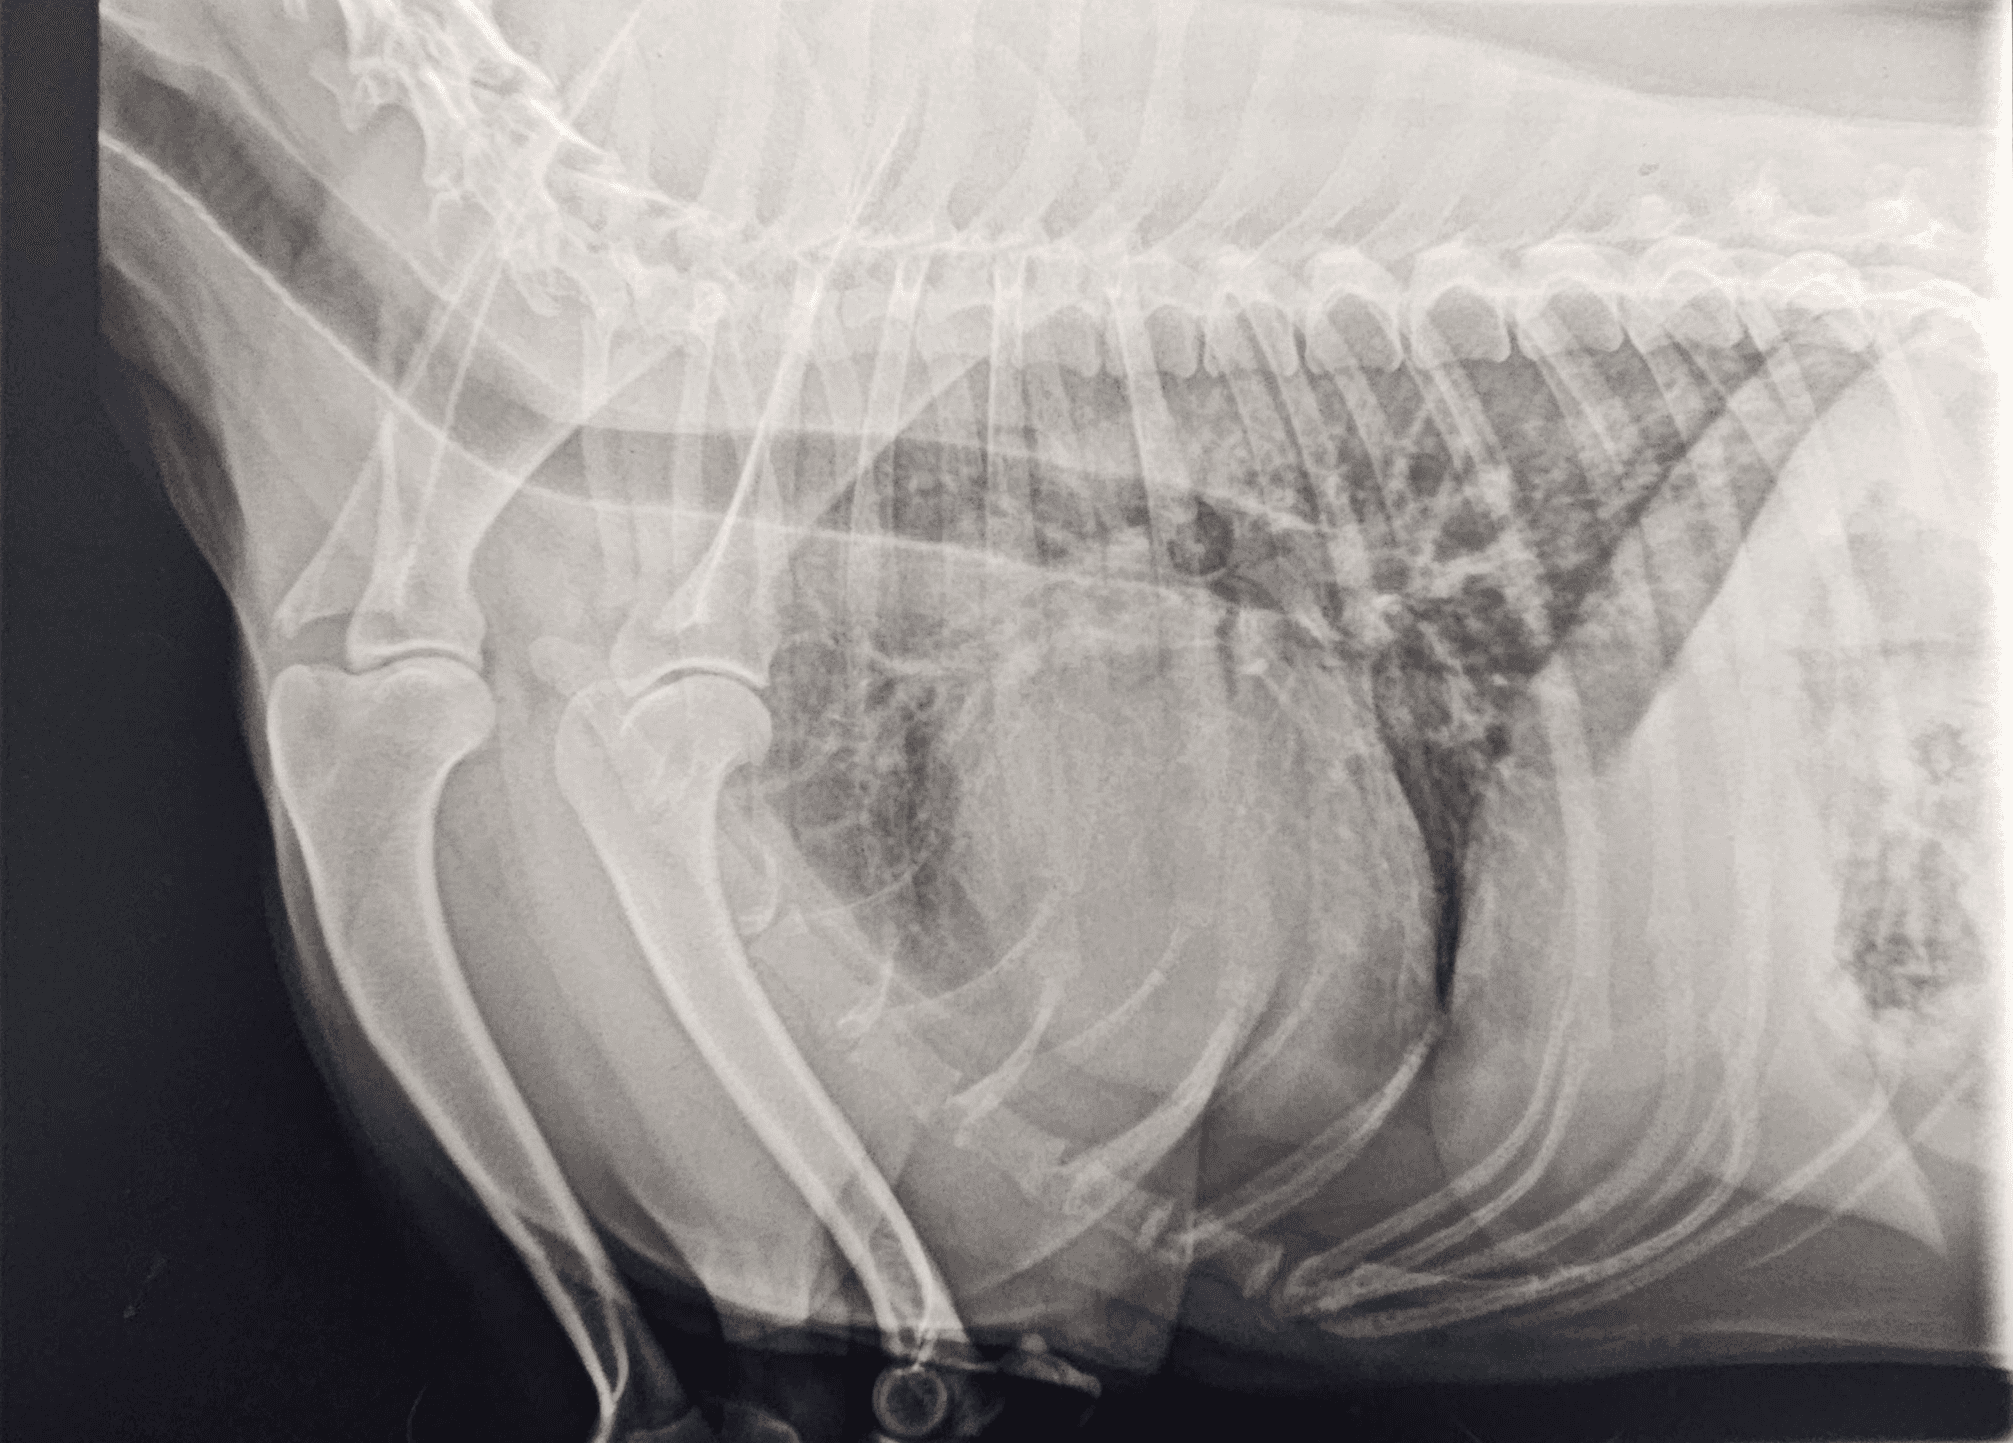

Pour cela, nous utilisons différentes techniques et matériels à notre disposition (échocardiographie, Doppler, ECG, radiographie thoracique, mesure de la pression artérielle, analyses sanguines, Holter ).

Radiographie Thoracique